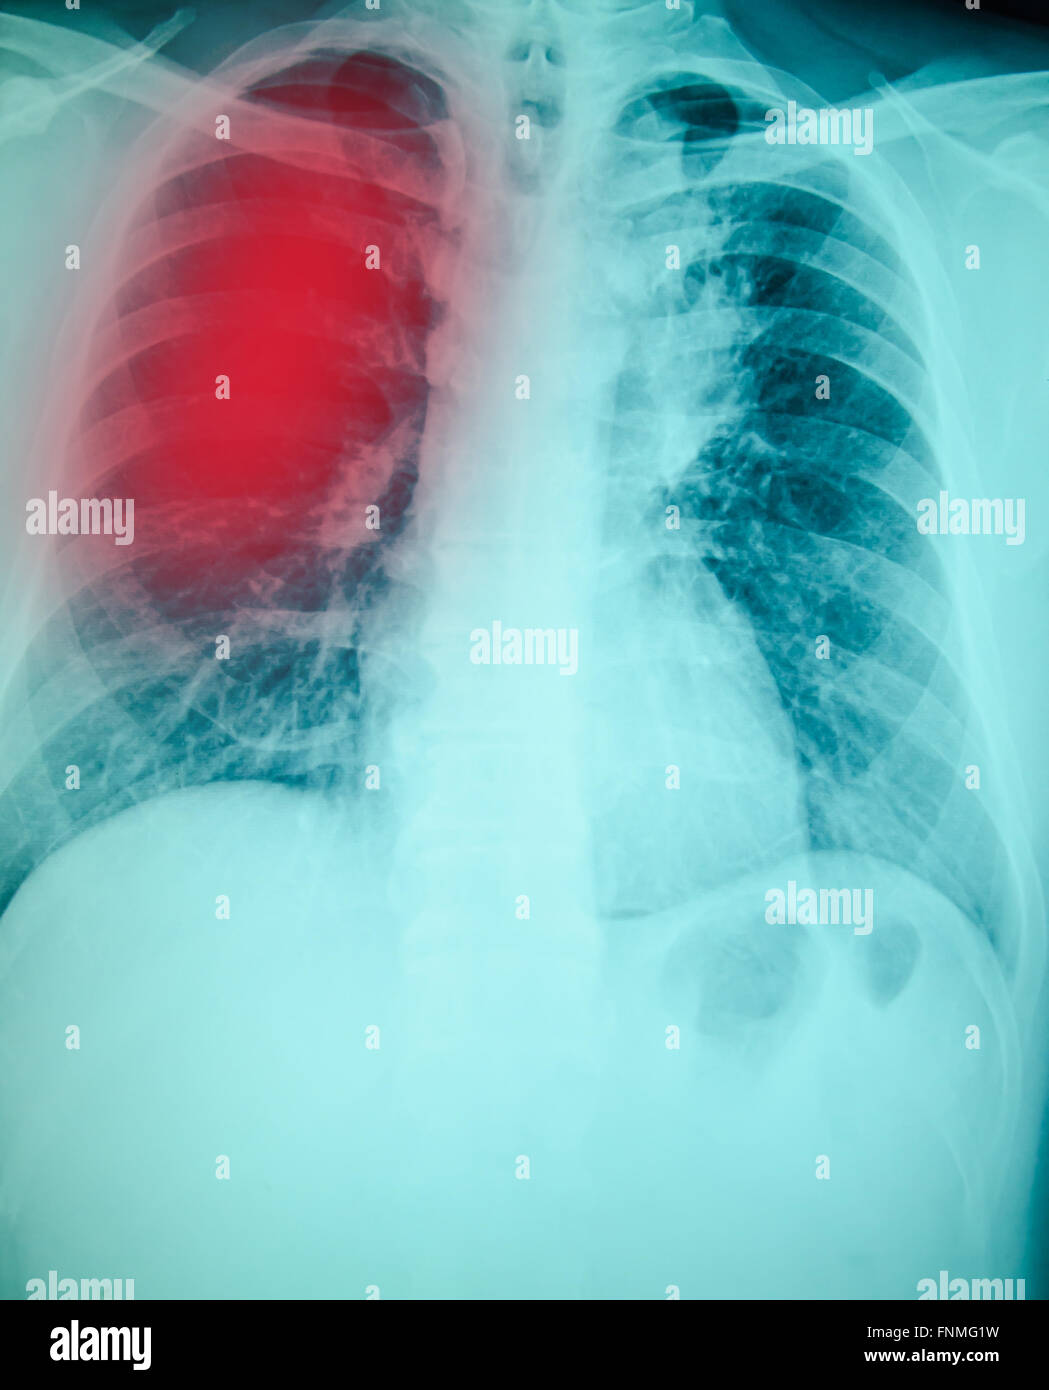

From www.alamy.com

xray of lung infection shown in red Stock Photo Alamy How To Identify Infection In Chest X Ray imaging plays an important role in the diagnosis of suspected pulmonary infection and may reveal useful signs at. A chest infection is an infection that affects the lower respiratory tract, including bronchitis, pneumonia, and. In fact every radiologst should be an expert in chest film. the answer is not always straightforward. chest radiograph is most helpful when. How To Identify Infection In Chest X Ray.

chest xray examination for diagnosis Pulmonary tuberculosis infection with both lung Stock How To Identify Infection In Chest X Ray the answer is not always straightforward. imaging plays an important role in the diagnosis of suspected pulmonary infection and may reveal useful signs at. In fact every radiologst should be an expert in chest film. chest radiograph is most helpful when it is normal and rules out pneumonia. A chest infection is an infection that affects the. How To Identify Infection In Chest X Ray.